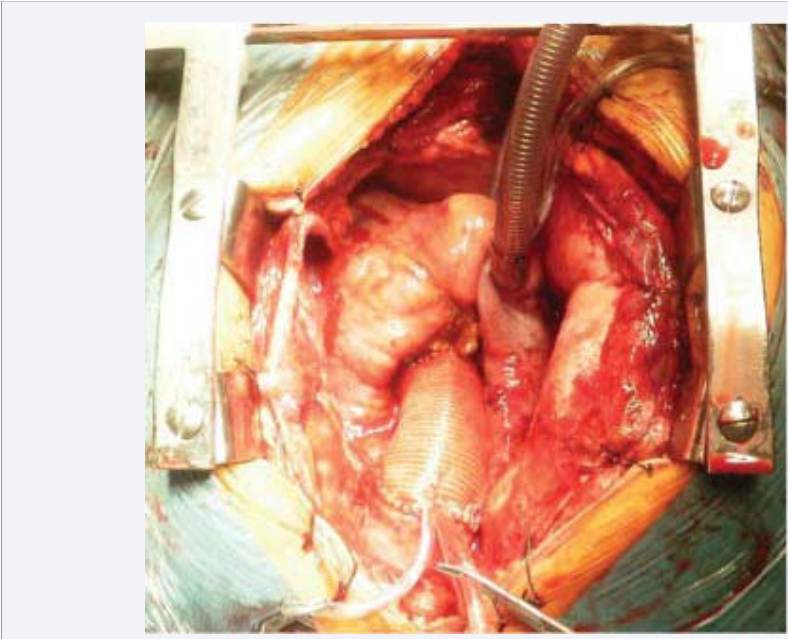

In this context, the patient underwent surgical resection of the aneurysm (Figure 5a),

Picture of the ascending aortic aneurysm in the operating  room.

Figure 5a: Picture of the ascending aortic aneurysm in the operating room.

with implantation of an aortic tube graft Jotec® # 30 (Figure 5b) and mechanical prosthesis in aortic position St. Jude® # 25 (Figure 5c), with good final result.

Aortic tube graft Jotec® # 30 in place.

Figure 5b: Aortic tube graft Jotec® # 30 in place.

Implantation of mechanical prosthesis in aortic position St.  Jude® # 25.

Figure 5c: Implantation of mechanical prosthesis in aortic position St. Jude® # 25.

Finally, the histopathological diagnosis of the surgical specimen was compatible with atherosclerosis (disruption of elastic fibers and smooth muscle cells that were partially replaced by extracellular matrix and lipids).